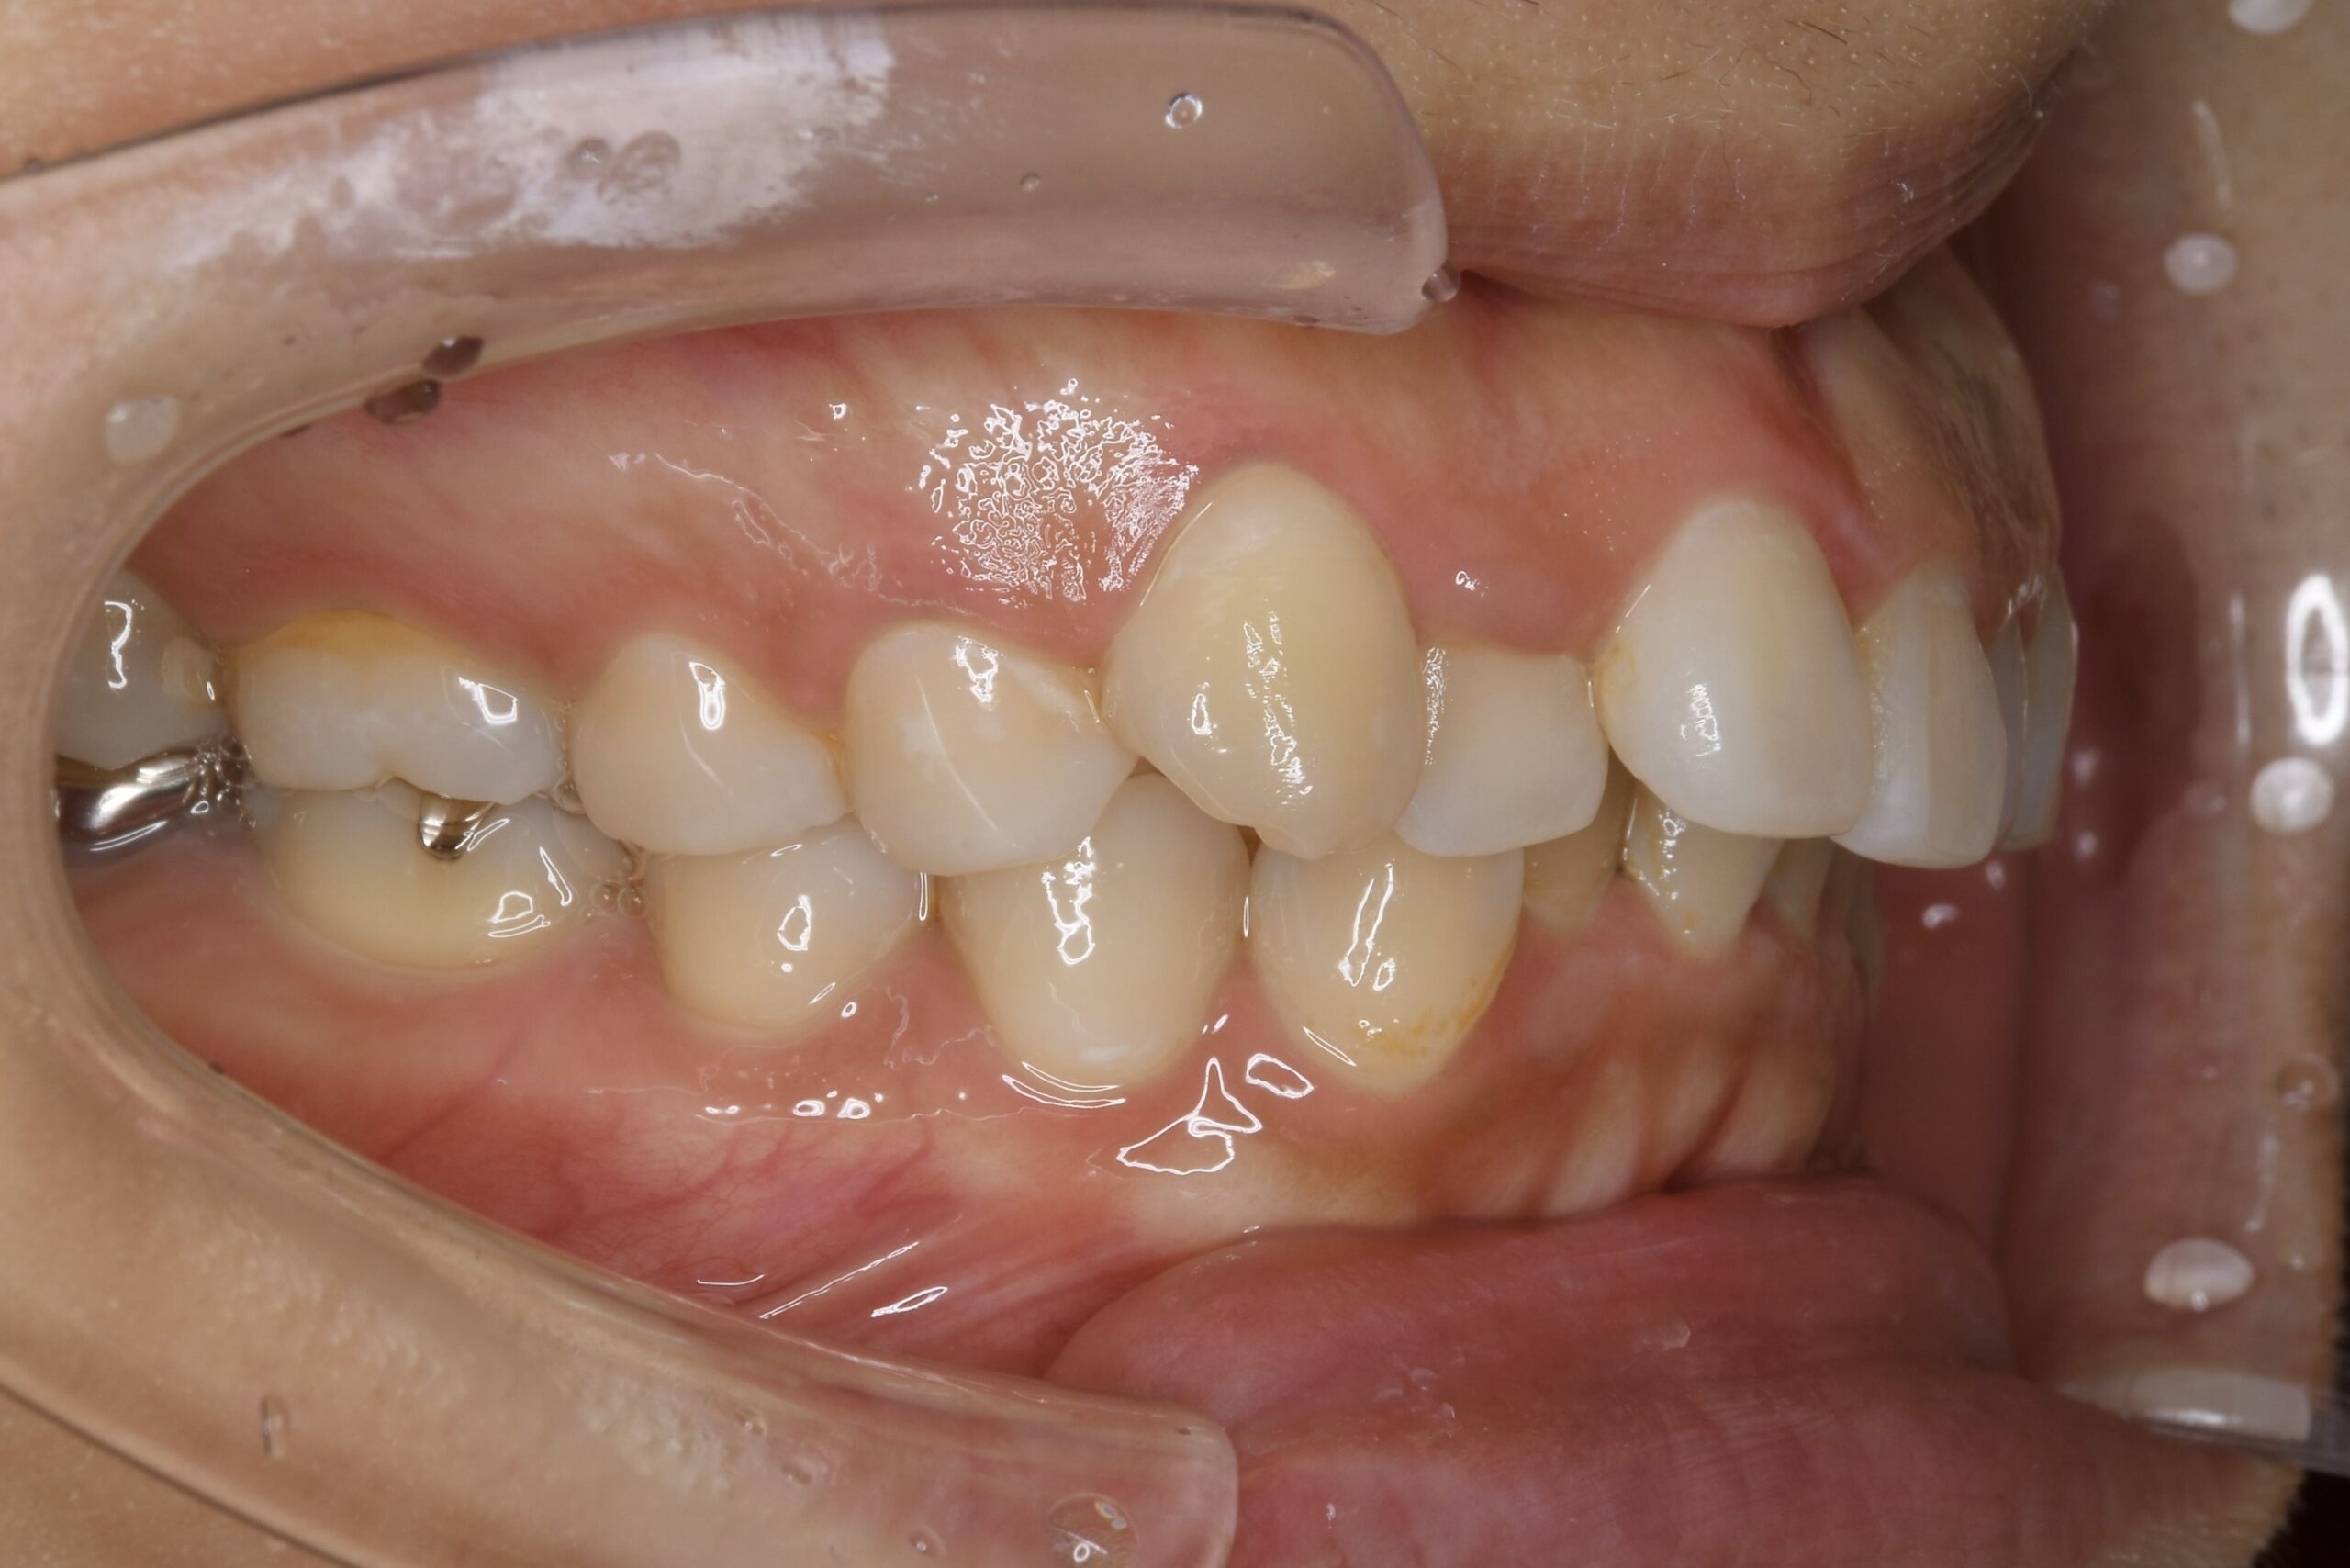

32歳 女性 治療期間:1年7ヶ月

AFTER

診断名・主な症状 叢生を伴う上顎前突

治療内容 上下とも歯を2本抜いて、上の前歯を後方に引きながら、でこぼこを治しました。

使用装置 マウスピース矯正装置(インビザライン)

抜歯部位 上 両側4番目

下 右側4番目、左側5番目

治療期間 1年7ヶ月